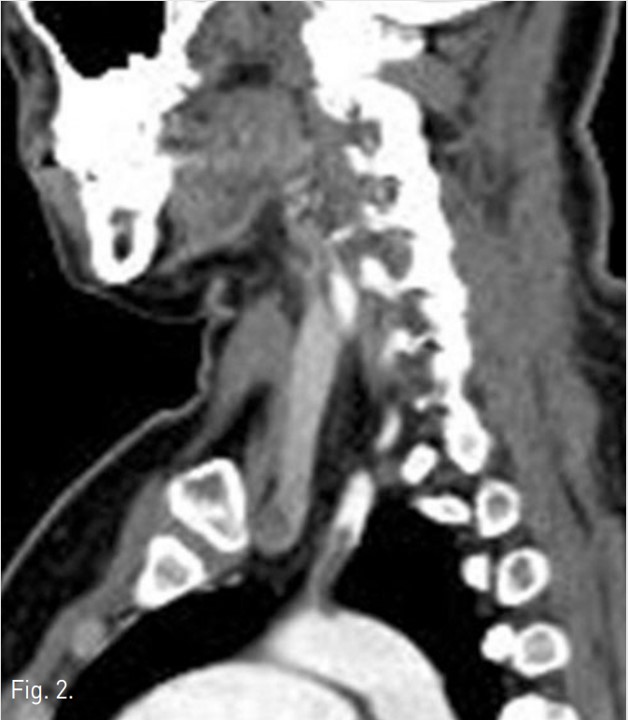

입원 3일 후 시행한 상지 CT 소견 상 left subclavian artery의 기시부에 약 3cm 길이의 thrombus가 보이며, 이 혈전은 aortic arch로 약 0.5cm 이상 튀어나와 있는 형태를 보였음(Fig. 1). 그리고 left radial artery와 left ulnar artery에도 thromboemboli가있음 (Fig. 2).

Fig. 1.

CT scan revealed 3cm sized partial thrombusprotruding into the aortic arch in origin of the left subclavian artery on axial(1, arrow) and sagittal scan (2).